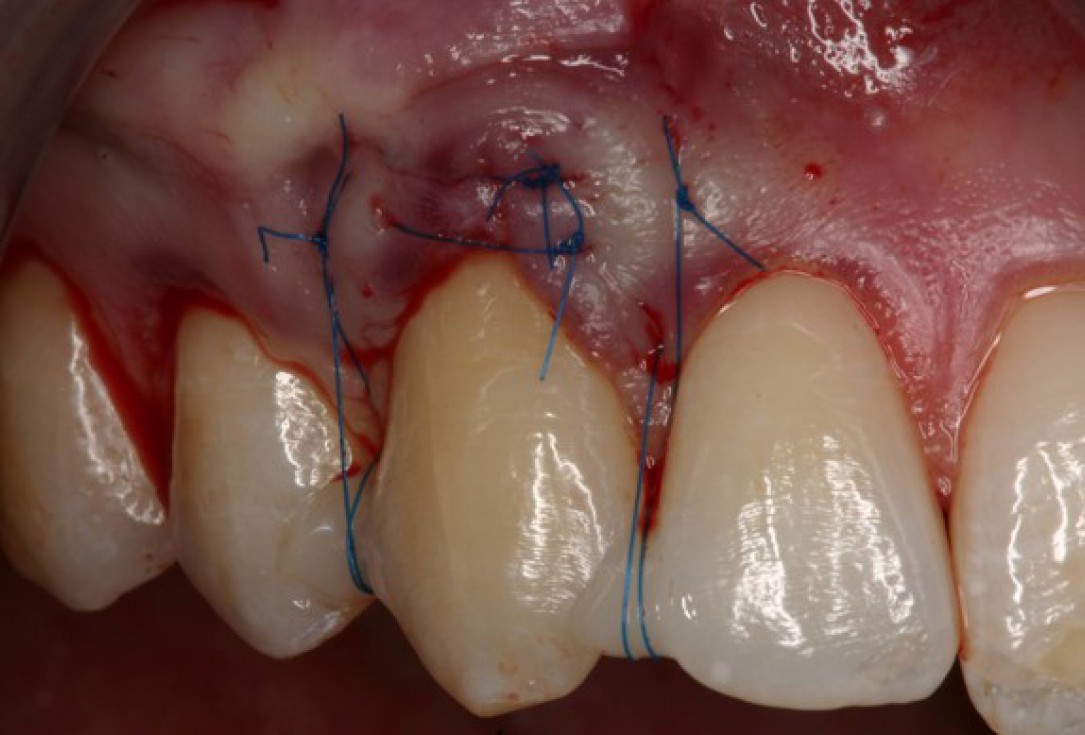

04/05 - Suturing to completely cover the mucoderm® matrix.Single gingival recession treated with the envelope technique in conjunction with mucoderm® - Prof. Dr. Dr. A. Kasaj